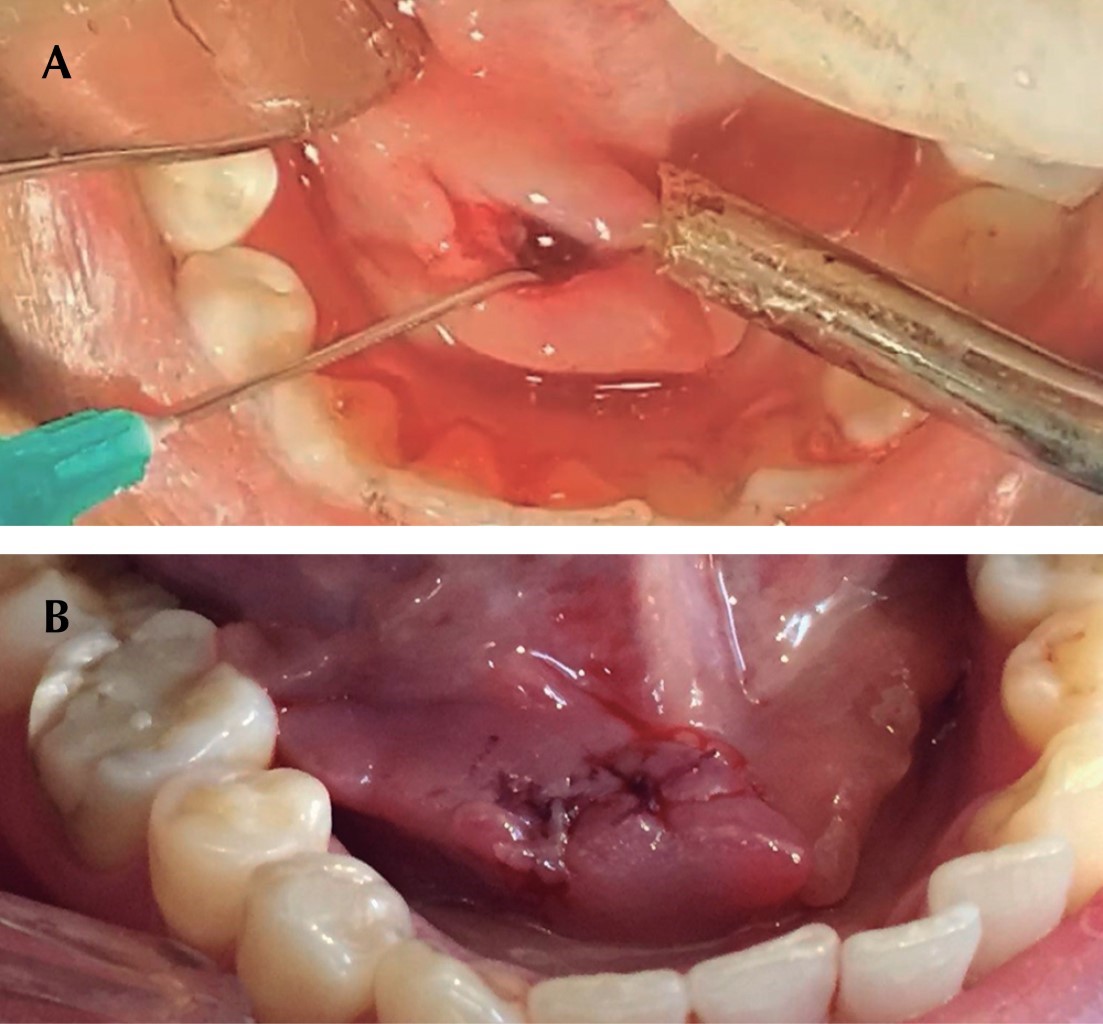

Previa infiltración de lidocaína 2% 1:100,000 haciendo bloqueo nervioso del nervio lingual, después se realizó una incisión lineal de 1 cm en la porción más prominente del sialolito sobre la mucosa, medial y paralela al trayecto del conducto de Wharton y del nervio lingual (Figura 4). Mediante unas pinzas mosquito (Halsted) se llevó a cabo la disección roma en dirección al sialolito la cual generó la expulsión del mismo en su totalidad fuera del conducto submandibular (Figura 5). Se realizó maniobra de digitopresión para ordeñar la glándula, con la finalidad de drenar la saliva estancada en el conducto submandibular, al momento de realizarla se observó salida de material purulento (Figura 6). Se efectuó la limpieza del lecho quirúrgico mediante irrigación con solución electrolizada de superoxidación. Se suturó la herida con Vicryl 4-0 mediante dos puntos simples (Figura 7). Por último se volvió a hacer la maniobra de digitopresión para observar la adecuada permeabilidad de la carúncula. La sialolitotomía se llevó a cabo sin complicaciones. En el postoperatorio inmediato se recetó antibiótico y analgésicos antiinflamatorios. La paciente fue citada siete días después de la intervención quirúrgica para su revisión postoperatoria. A la exploración no había presencia de inflamación extraoral, así como ausencia de infección, dolor, sangrado y dehiscencia de la herida quirúrgica (Figura 8).

Figura 4

Figura 5

Figura 6

Figura 7